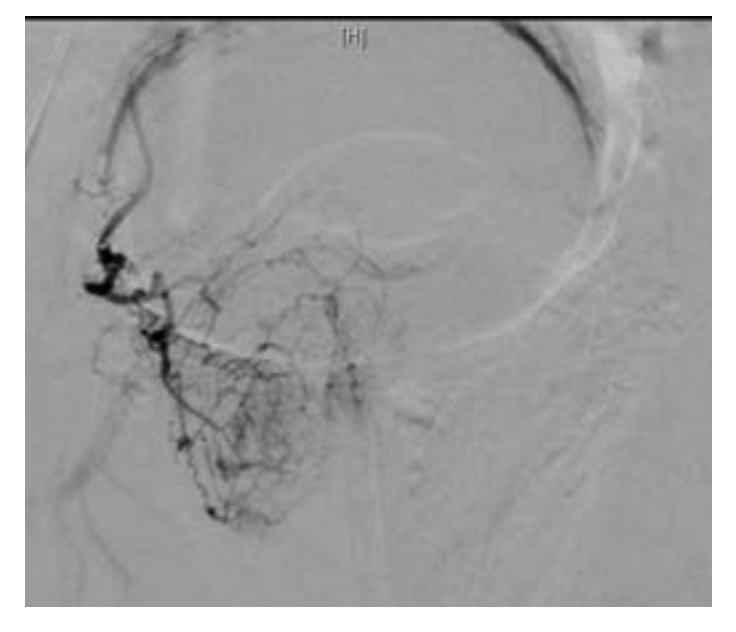

Initial arterial access was obtained and a pigtail catheter was advanced into the abdominal aorta to the level of the aortic bifurcation. Using a hybrid angio-CT unit (Nexaris, Siemens Healthcare AG, Forchheim, Germany), a CTA was obtained to delineate arterial anatomy and determine the pattern of glandular reperfusion. Multiplanar reconstruction was performed using syngo DynaCT and Embolization Guidance software (Siemens Healthcare AG, Forchheim, Germany). These images demonstrated no perfusion from either the previously treated right or left prostatic arteries, which now appeared markedly attenuated. Instead, the majority of the gland had been revascularized through a distal internal pudendal artery collateral on the right, with more proximal branches perfusing the cavernosal tissues (Figure 7). These cavernosal branches also appeared to be the sole supply to the cavernosal tissues on the right, and therefore critical to avoid nontarget embolization to penile tissues. The CTA/Embolization Guidance data sets were then fused to create an overlay of the vessel trajectory to be displayed during 2D fluoroscopy. Given the vessel tortuosity and small caliber size (Figure 8), an Excelsior SL-10 microcatheter (Stryker, Fremont, CA) and 014’ Synchrosoft microwire (Stryker) were used to select the terminal branch of the internal pudendal artery distal to the cavernosal branches. Angiography from this location demonstrated brisk antegrade flow with perfusion of the central gland without extra-prostatic perfusion (Figure 9). Embolization was performed to stasis using 300-500 micron particles. Completion angiography demonstrated no further prostatic perfusion and preservation of more proximal cavernosal branches. The patient had an uneventful postoperative course, and by 1 month post PAE his IPSS/QoL was 3/0, respectively.